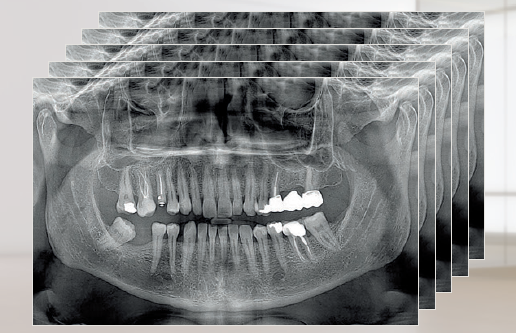

X-Radius Trio Plus воплощает новейшие технологии двухмерной и трехмерной визуализации в сочетании с простотой использования. В качестве модульного решения устройство предоставляет бесчисленные возможности модернизации и включает в себя удобное программное обеспечение, разработанное совместно с университетскими специалистами и рентгенологами. Теперь доступна DC-версия: стоматологи могут выбрать новейшую технологию прямого преобразования как для PAN-, так и для CEPH-датчиков. Обеспечивая самые современные клинические характеристики и превосходное качество изображений, X-Radius Trio Plus также предназначен для защиты здоровья пациентов за счет минимизации радиационного облучения всеми возможными способами.

X-Radius Trio Plus предоставляет полный спектр возможностей для двухмерных и трехмерных исследований, которые поддерживаются функциями программного обеспечения для оптимизации результатов диагностики. Trio Plus — это гибридная система, использующая технологию конусно-лучевой томографии для объемного сканирования и высокопроизводительные фильтры, обеспечивающие наилучшую клиническую 2D-рентгенографию, доступную на сегодняшний день. Модульная платформа позволяет менять первоначальную конфигурацию аппарата различными способами, чтобы подстраиваться под текущие потребности лечения. X-Radius Trio Plus был разработан для облегчения переключения платформы от одной задачи к другой, уменьшая время простоя в процессе переключения, и как результат — оптимизации инвестиций.

Преобразовываясь напрямую в электрические сигналы, минуя стадию преобразования в свет, рентгеновские фотоны остаются в неизменном виде до тех пор, пока не сформируют панорамное изображение. Таким образом благодаря минимальному рассеиванию сигнала технология позволяет генерировать значительно более четкие изображения, чем те, которые получены с использованием традиционной технологии. Это гарантирует высококонтрастные экстраоральные 2D-снимки при низких дозах облучения: панорамные изображения и телерентгенограммы, визуализацию верхнечелюстных пазух, ВНЧС, зубных рядов и прикуса.